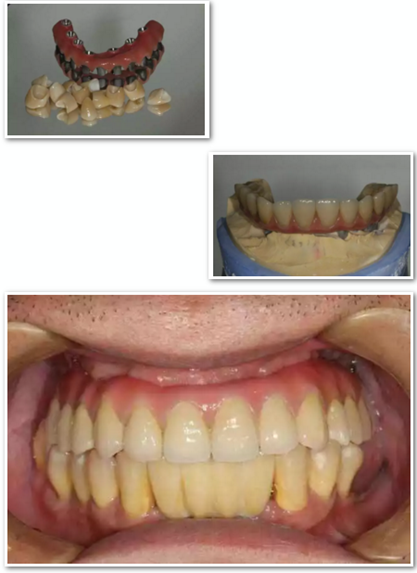

術(shù)后拍攝全景片。

最終修復(fù),帶上假牙。